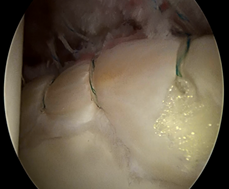

在持续牵引下首先进入髋关节中央间室,在70度镜下进行关节探查,清理增生的炎性滑膜、取出游离体、处理软骨损伤及切除病变的髋臼盂唇;对于FIA患者,磨削骨性髋臼缘去除pincer撞击,如果不存在Pincer撞击,则仅需磨削髋臼缘去皮质化,新鲜化髋臼缘形成一个弧形的、光滑的渗血骨床。对损伤的盂唇尽量予以缝合(采用可吸收锚定)。然后在非牵引下进入外周间室,30度镜下对股骨头颈处的Cam撞击进行股骨头颈成型,避免修复的盂唇组织发生撞击。(左图:关节镜下缝合盂唇;右图:缝合后的盂唇)

髋关节镜下进行盂唇修复术具有明显的创伤小、恢复快等优势。目前髋关节镜下进行盂唇修复术后的临床效果十分满意。Phillipon等发现,曲棍球运动员髋臼盂唇损伤后,1年之内手术治疗的运动员要比伤后1年以后再手术治疗运动员更快重返赛场,临床效果也更好。因此,髋臼盂唇损伤后保守效果欠佳的要早期进行手术治疗。